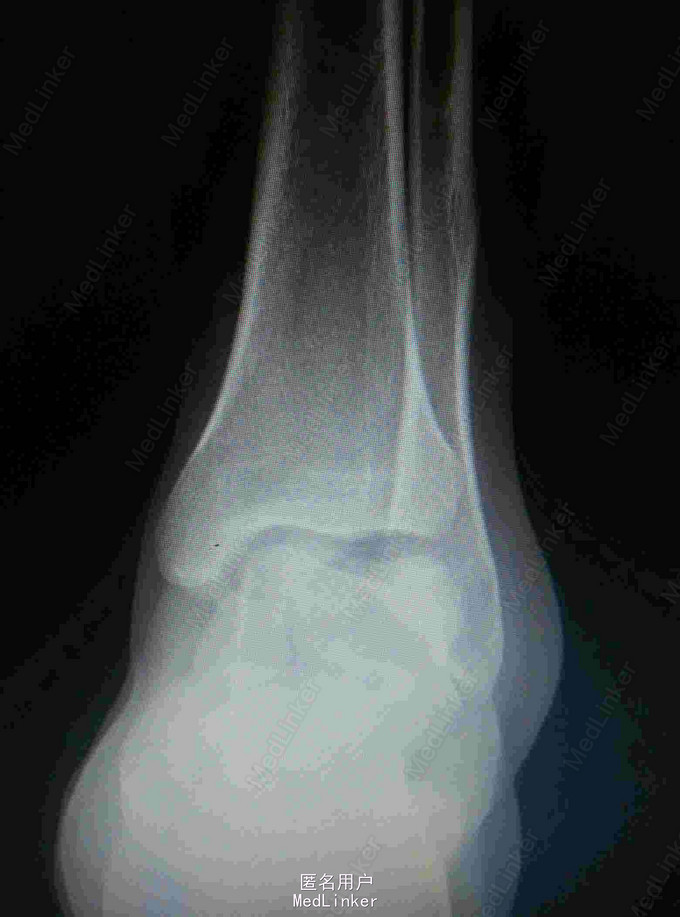

患者,男,27岁,高处坠落致左踝部肿痛,活动受限

完善X线片及CT扫描检查